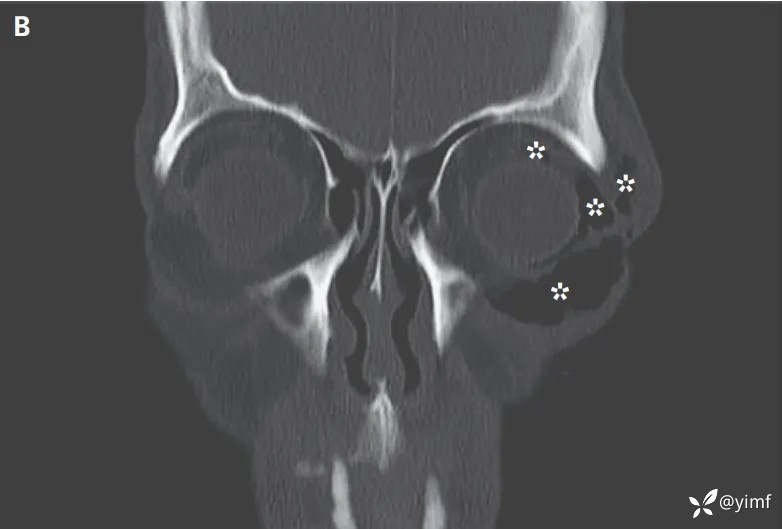

面部计算机断层扫描显示眶周皮下(图B,星号)、球后气肿、眶下缘骨折,左侧有一个完整的眼球体。